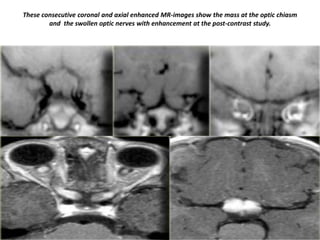

These consecutive coronal and axial enhanced MR-images show the mass at the optic chiasm

and the swollen optic nerves with enhancement at the post-contrast study.